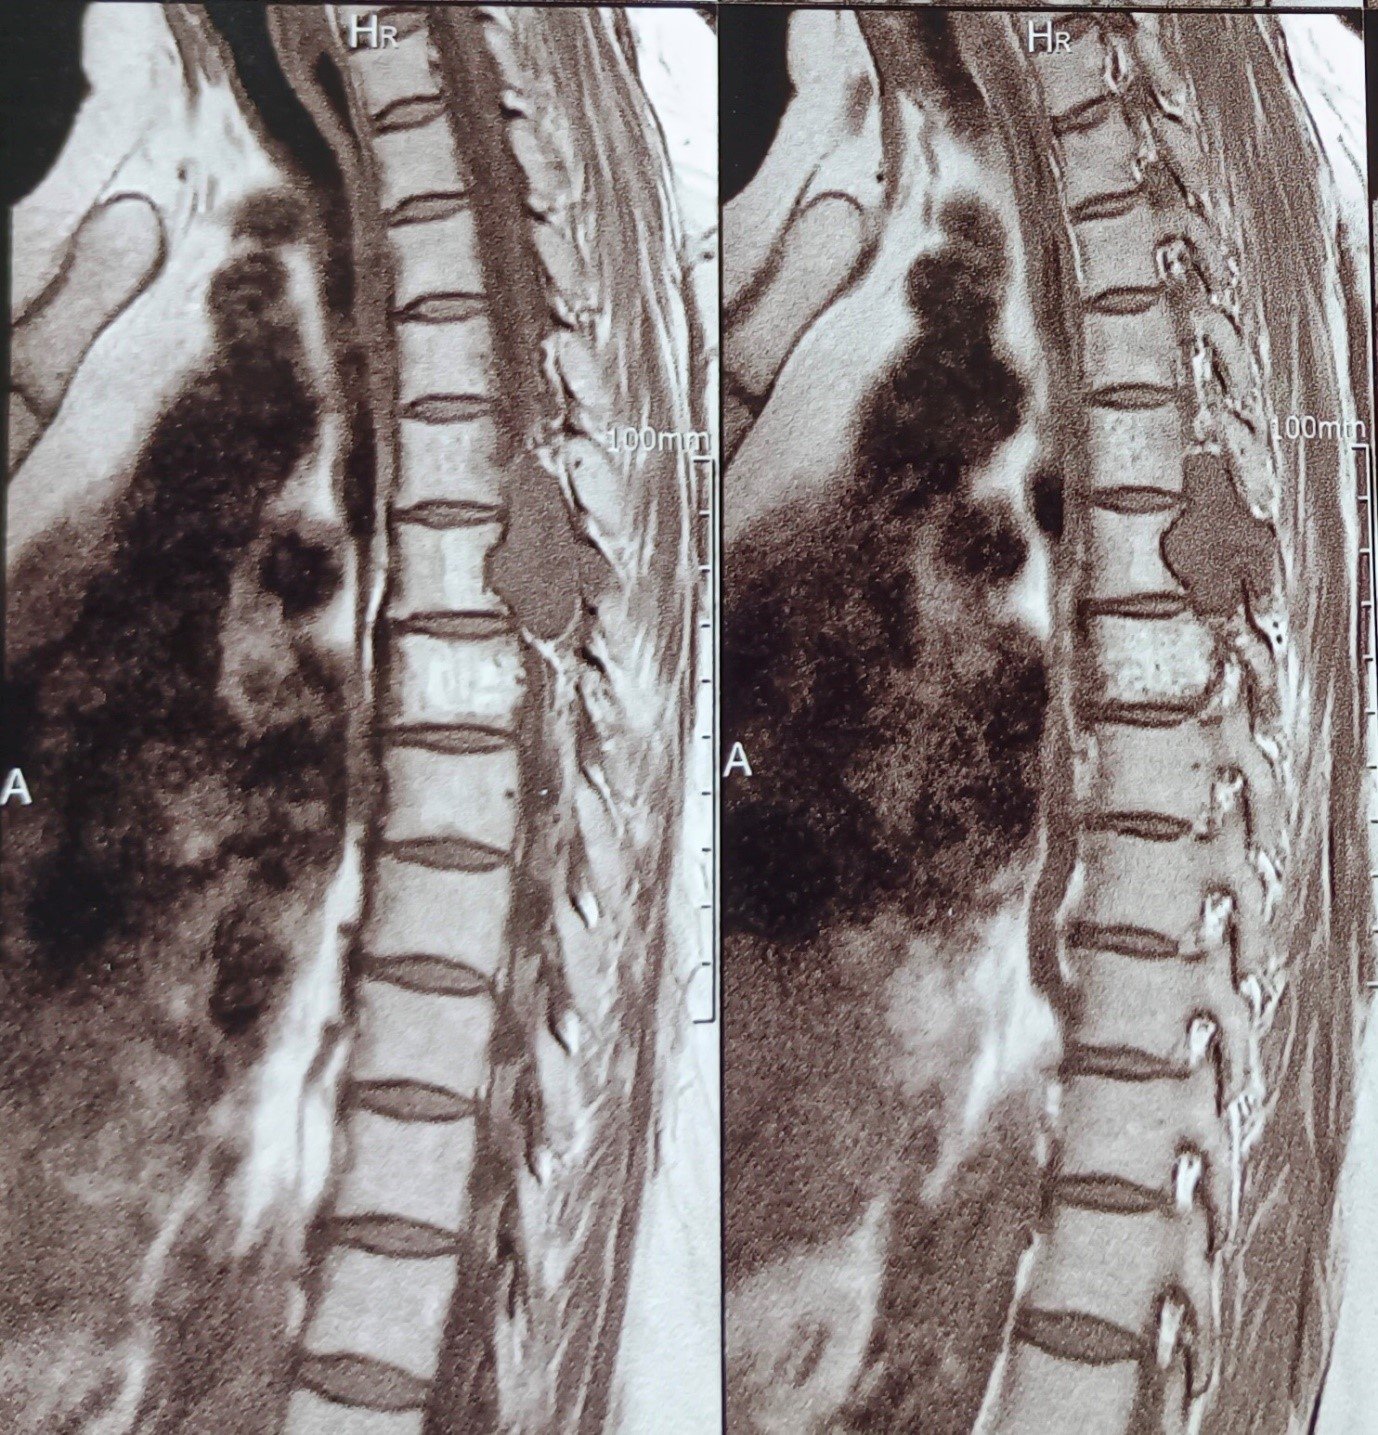

Cervical Myelopathy Expert Care by Dr. Nitish Agrawal – Best Spine Surgeon in Pune Cervical Myelopathy is a serious spinal condition in which the spinal cord in the neck (cervical spine) becomes compressed. This compression is most commonly caused by degenerative changes in the spine, such as cervical disc prolapse,…